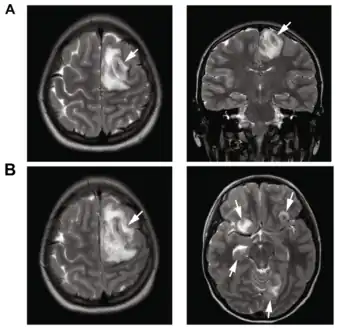

T2-weighted MRI showing liquefied, necrotic brain tissue as a result of GAE caused by an infection of Acanthamoeba, genotype T18